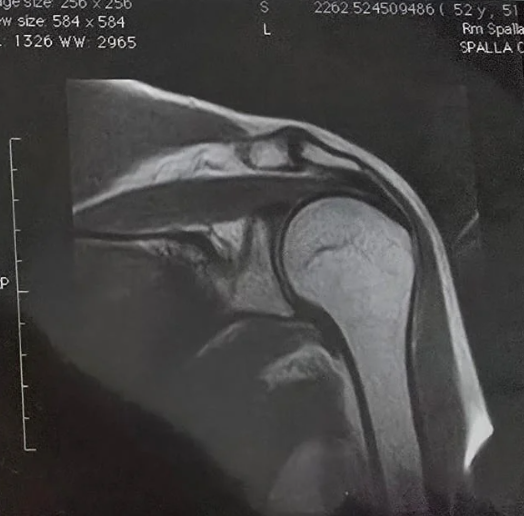

Recupero da tendinopatia, doppia calcificazione della cuffia dei rotatori (spalla sx)

Paziente: donna, 52 anni

Quadro clinico: dolore subacuto alla spalla sx con limitazione funzionale in elevazione e rotazione. Valutazione diagnostica: tendinopatia della cuffia dei rotatori con doppia calcificazione intratendinea. Dolore notturno e deficit di ROM attivo (Range of Motion attivo).